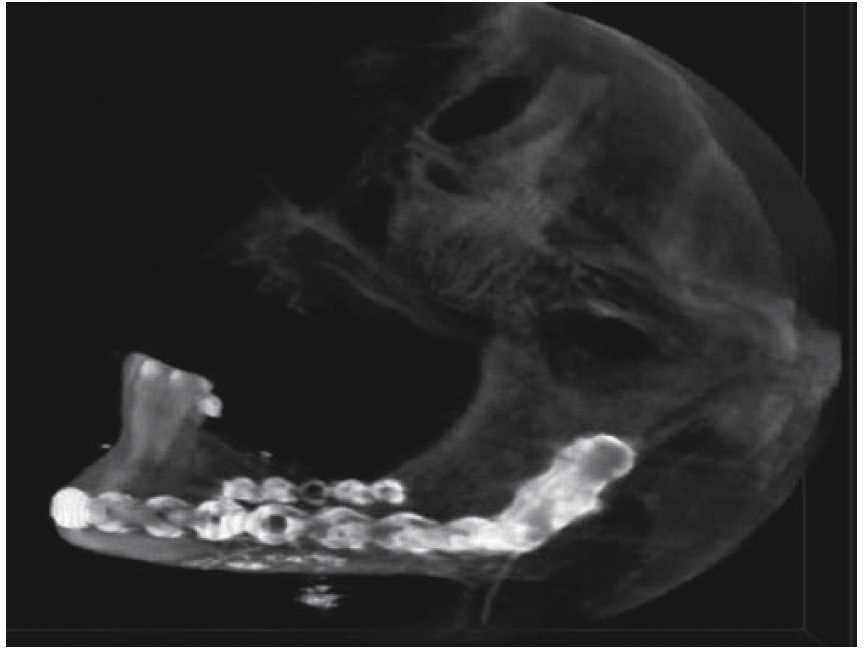

The second surgical event took place seven days later, performing extraoral approach. The fracture was reduced and bone edges were fixated with a 2.4 precontoured mandibular reconstruction plate (Figure 6). Occlusal stability was verified before suturing tissues and bar arches were removed (Figure 7). The patient remained in hospital for seven days, after which he showed suitable occlusion and appropriate healing. Suture points were then removed, a control study was performed and the patient was discharged. The patient did not attend control visits due to the fact that he was incarcerated.

Treatment was initiated with immunization, antibiotic therapy, analgesia, extraction of septic foci and mechanical cleansing of the wound. The patient lacked removable or partial prostheses, so in order to establish inter-maxillary relationship and facial height, gunning splints were manufactured in order to establish inter-maxillary relationship (Figure 13). After ten days of initial treatment, the patient exhibited suitable alveolar healing, with presence of non-fetid secretion at the level of the mandibular wound. The second procedure was then undertaken with extra-oral approach; a 2.4 mandibular reconstruction plate and a 2.0 bone segment plate were used (Figures 14 and 15). The patient was discharged, and she attended periodic assessment visits which showed suitable healing (Figure 16) and adequate mandibular mobility. Three weeks after reconstruction, the patient was instructed to initiate prosthetic treatment in order to achieve rehabilitation.